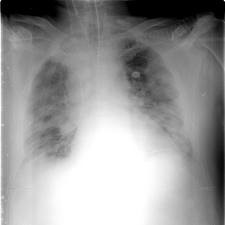

Опухоли легкого

Опухоли легкого – это проявление раковой болезни, причинами которой становятся курение, негативное воздействие асбеста, мышьяка, галогенов, загрязнений воздуха, радиоактивных веществ.

На ранних стадиях появляются кашель, кровохарканье, боли в груди, одышка, повышение температуры. Часто течение болезни напоминает воспаление легких, необходимо тщательное исследование. Читать далее